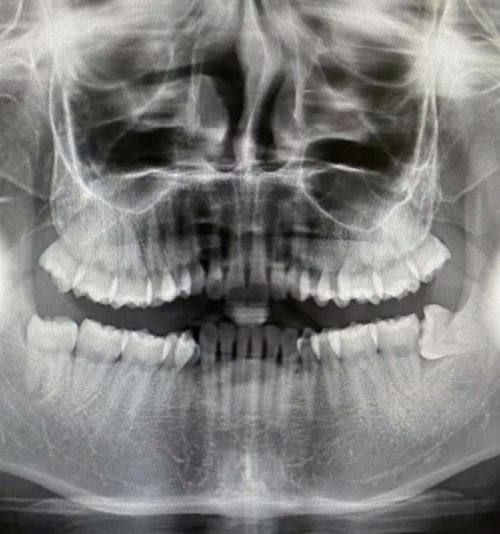

1. 数字种植正畸:门诊引进CBCT(口腔CT)、智能化扫描仪等精良设备,能快速获取患者口腔数据,使种植和正畸治疗更加精细、效率高。

16. 口腔全景片:100 - 300元

17. 口腔CT:300 - 800元